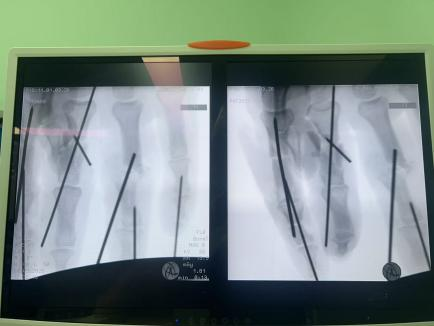

骨折內(nèi)固定+肌腱神經(jīng)修復(fù):不僅要讓手指“活”,更要讓手指“能用”。

面對這些困難,許攀峰團(tuán)隊(duì)沒有卻步,沉著應(yīng)戰(zhàn)。他們先是為骨折的手指進(jìn)行精準(zhǔn)內(nèi)固定,重建骨骼支撐;隨后,在顯微鏡下,一根根尋找斷裂的血管、神經(jīng)和肌腱——清創(chuàng)、修剪、吻合、通血……每一步都如履薄冰,每一次打結(jié)都需屏息凝神,手術(shù)室內(nèi),寂靜無聲,只有時鐘的滴答聲在空氣中回蕩,仿佛在為這場生命的接力默默計(jì)時。

1小時、2小時、3小時…… 時間在寂靜中流逝,顯微鏡下,一雙雙手在無聲地忙碌著,他們的動作嫻熟而精準(zhǔn),如同在跳一場無聲的生命舞蹈。終于,將近5個小時后,最后一針縫線完成。松開止血鉗,所有再植的手指瞬間恢復(fù)紅潤,指腹飽滿,毛細(xì)血管反應(yīng)靈敏——手術(shù)成功了!這一刻,手術(shù)室內(nèi)壓抑的氣氛瞬間被打破,許攀峰團(tuán)隊(duì)成員們臉上露出了欣慰的笑容。